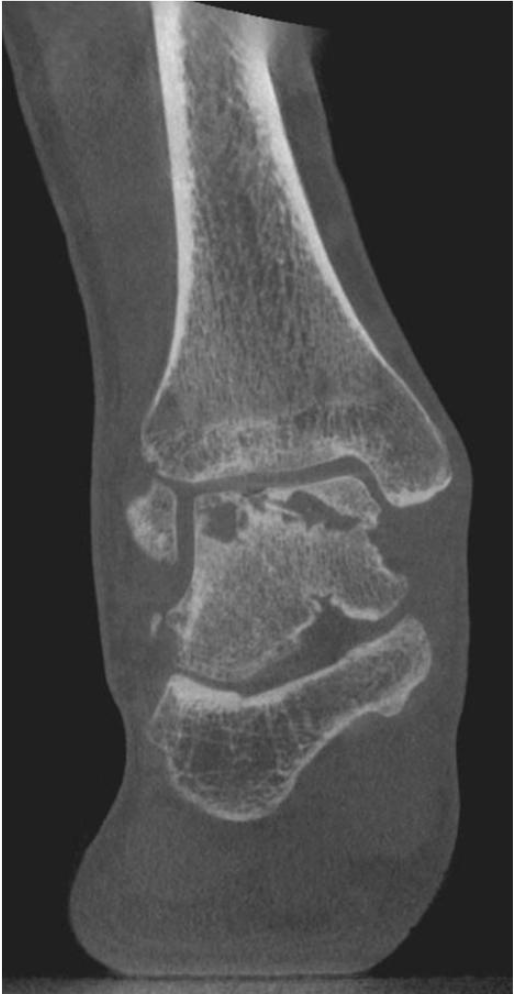

通过逆行钻孔实现松质骨水肿或囊肿的减压。适应症:软骨表面完整时的骨髓水肿或软骨下囊肿减压,仅限于 Berndt 和 Harty 分期的 I 期和 II 期。

逆行钻孔逆行钻孔可通过X线透视或计算机辅助设备结合专用导向器械进行,使用 1.1-2.4mm 不同直径克氏针。原则上选择针径时需确保可多次钻孔,且克氏针足够稳固不折断。